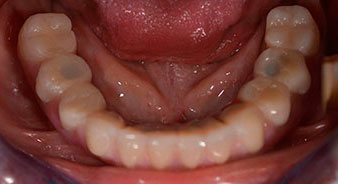

La paziente, 64 anni, presenta una dentatura residua di denti 38, 33 e 43 e una protesi combinata innestata nella mandibola (Fig. 1 e 2).